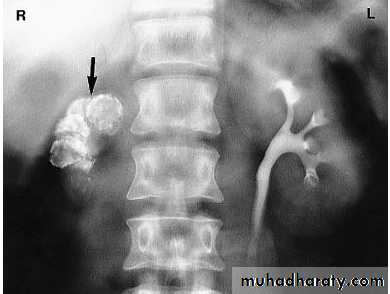

Crossed fused renal ectopia

Left duplex system. The lower moiety inserts into the bladder trigone

(not shown), whereas the upper moiety ureter usually has an ectopic distal

insertion (see text).